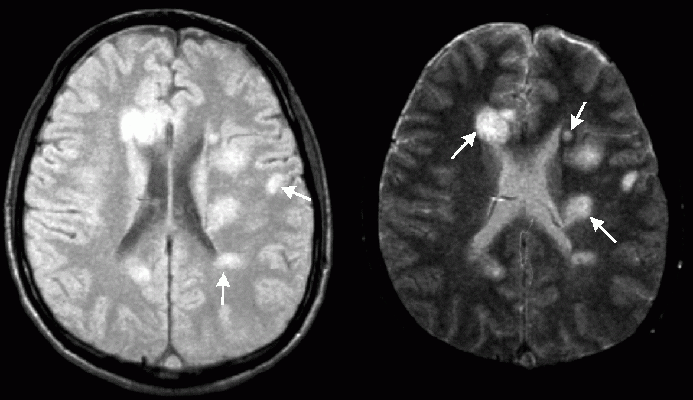

Рассеянный склероз - это хроническое аутоиммунное заболевание, которое поражает центральную нервную систему и поражает главным образом молодых людей. В то время как в прошлом диагноз рассеянного склероза был очень серьезным сообщением, и очень мало что можно было сделать, чтобы отсрочить инвалидность, в настоящее время врачи могут значительно снизить активность заболевания и замедлить его прогрессирование. Тем не менее, ранняя диагностика, соответствующее лечение и мониторинг течения заболевания имеют важное значение. Только так пациенты могут продолжать вести максимально полную жизнь. Откуда она взялась? Рассеянный склероз был впервые описан французским неврологом Жаном-Мартином Шарко (1825-1893) в 1848 году. Несмотря на то, что болезнь имела свое название, ее возможности диагностики и лечения были очень ограничены. Ее лечили золотом, электротерапией или гидротерапией. Исследование Луи-Антуана Ранвье (1835-1922), который описал структуру нервных волокон вместе с их защитной миелин